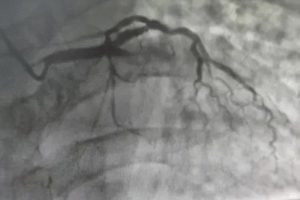

造影結果顯示

前降支中段閉塞

胸部異樣別忽視,及時就診是關鍵!